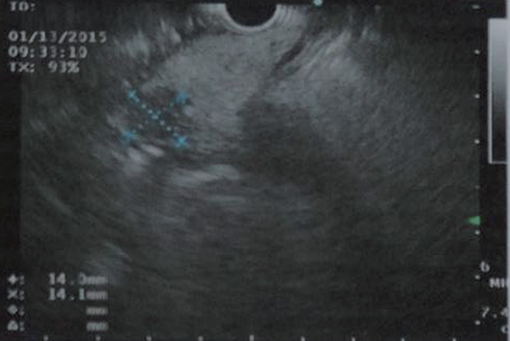

Se le realizó endosonografía para complementar estudio, la cual mostró una lesión de 11 x 9,4 mm en la cabeza del páncreas (Figura 1). Se indicó Octreoscan para completar estudio, en donde se identificó lesión focal en cabeza pancreática con presencia de receptores de somatostatina, compatible con insulinoma (Figura 2).

Figura 1. Endosonografía de páncreas que muestra imagen ovalada e hipodensa de lesión de 11 x 9,4 mm en cabeza de páncreas